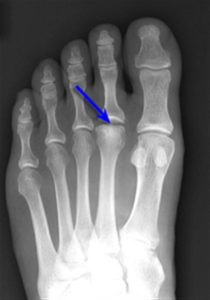

Freiberg’s Infraction (Avascular Necrosis of the 2nd Metatarsal)

Freibergs disease or avascular necrosis of the metatarsal head is a rare, painful bone disorder. It is most commonly seen in adolescence between 12 and 18 years of age.

There can be pain, swelling, redness or warmth on the top of the foot. The diagnosis is confirmed by x-ray and a complete examination at the Foot and Ankle Centre of Victoria.